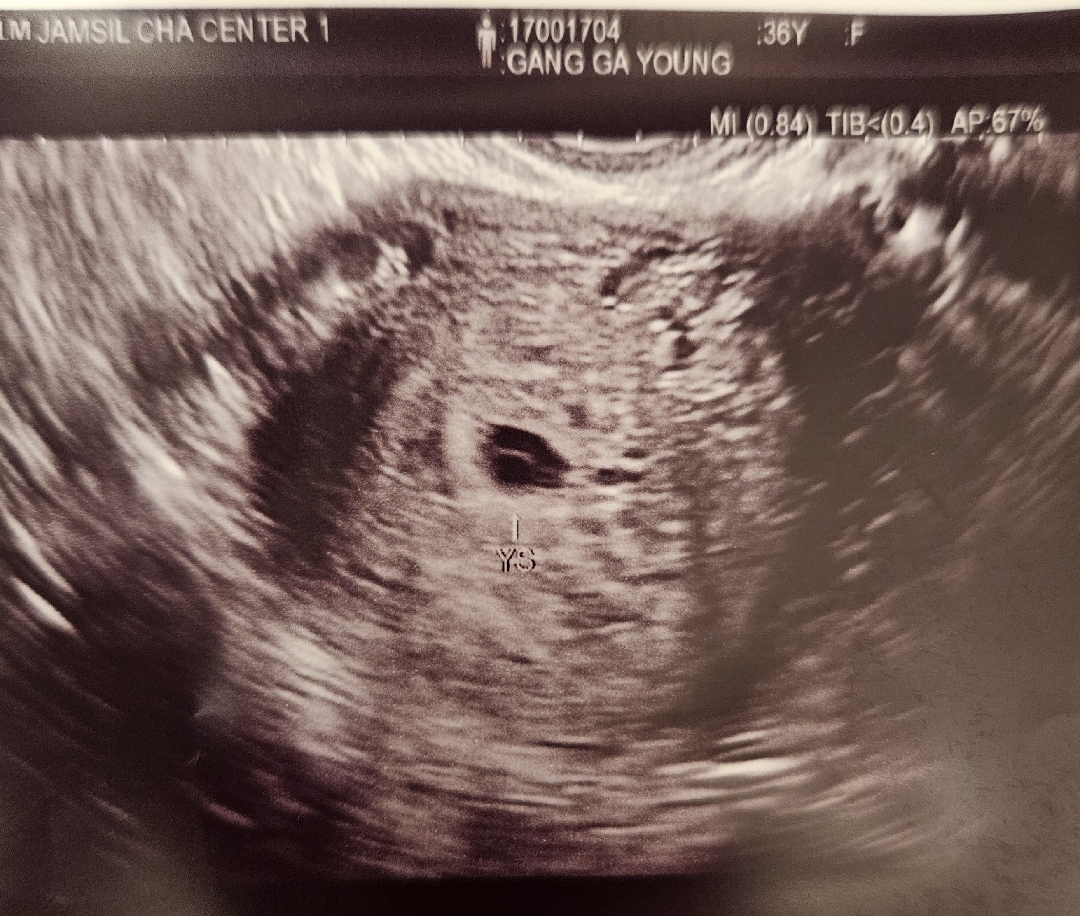

5/21 막생 6/4 인공수정 6/27 아기집 0.3cm (5주 2일차) 7/4 아기집 0.6cm / 난황 0.3cm (6주 2일차) 생리주기는 32일정도에요 착상이 늦은건지뭔지... 주수보다 작다고 하셨는데 이번주 토요일에 심장소리 들으면 괜찮다하시는데 저는 왜캐 남들보다 아기집이 너무 작은거같죠..ㅠㅠ 어떠신것같나요?? 심장소리 들을수있을까요 ...ㅠㅠ